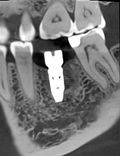

We chose a staged approach. First, the tooth was carefully removed, allowing the tissues to heal naturally. After about six weeks, the implant was placed using precise digital planning. A temporary crown was then fitted to shape a natural gum contour, followed by the final permanent crown.

The tooth was fully restored. The implant is stable, the gum looks natural, and oral hygiene is comfortable. The patient returned to his normal life with a reliable, long-term solution.